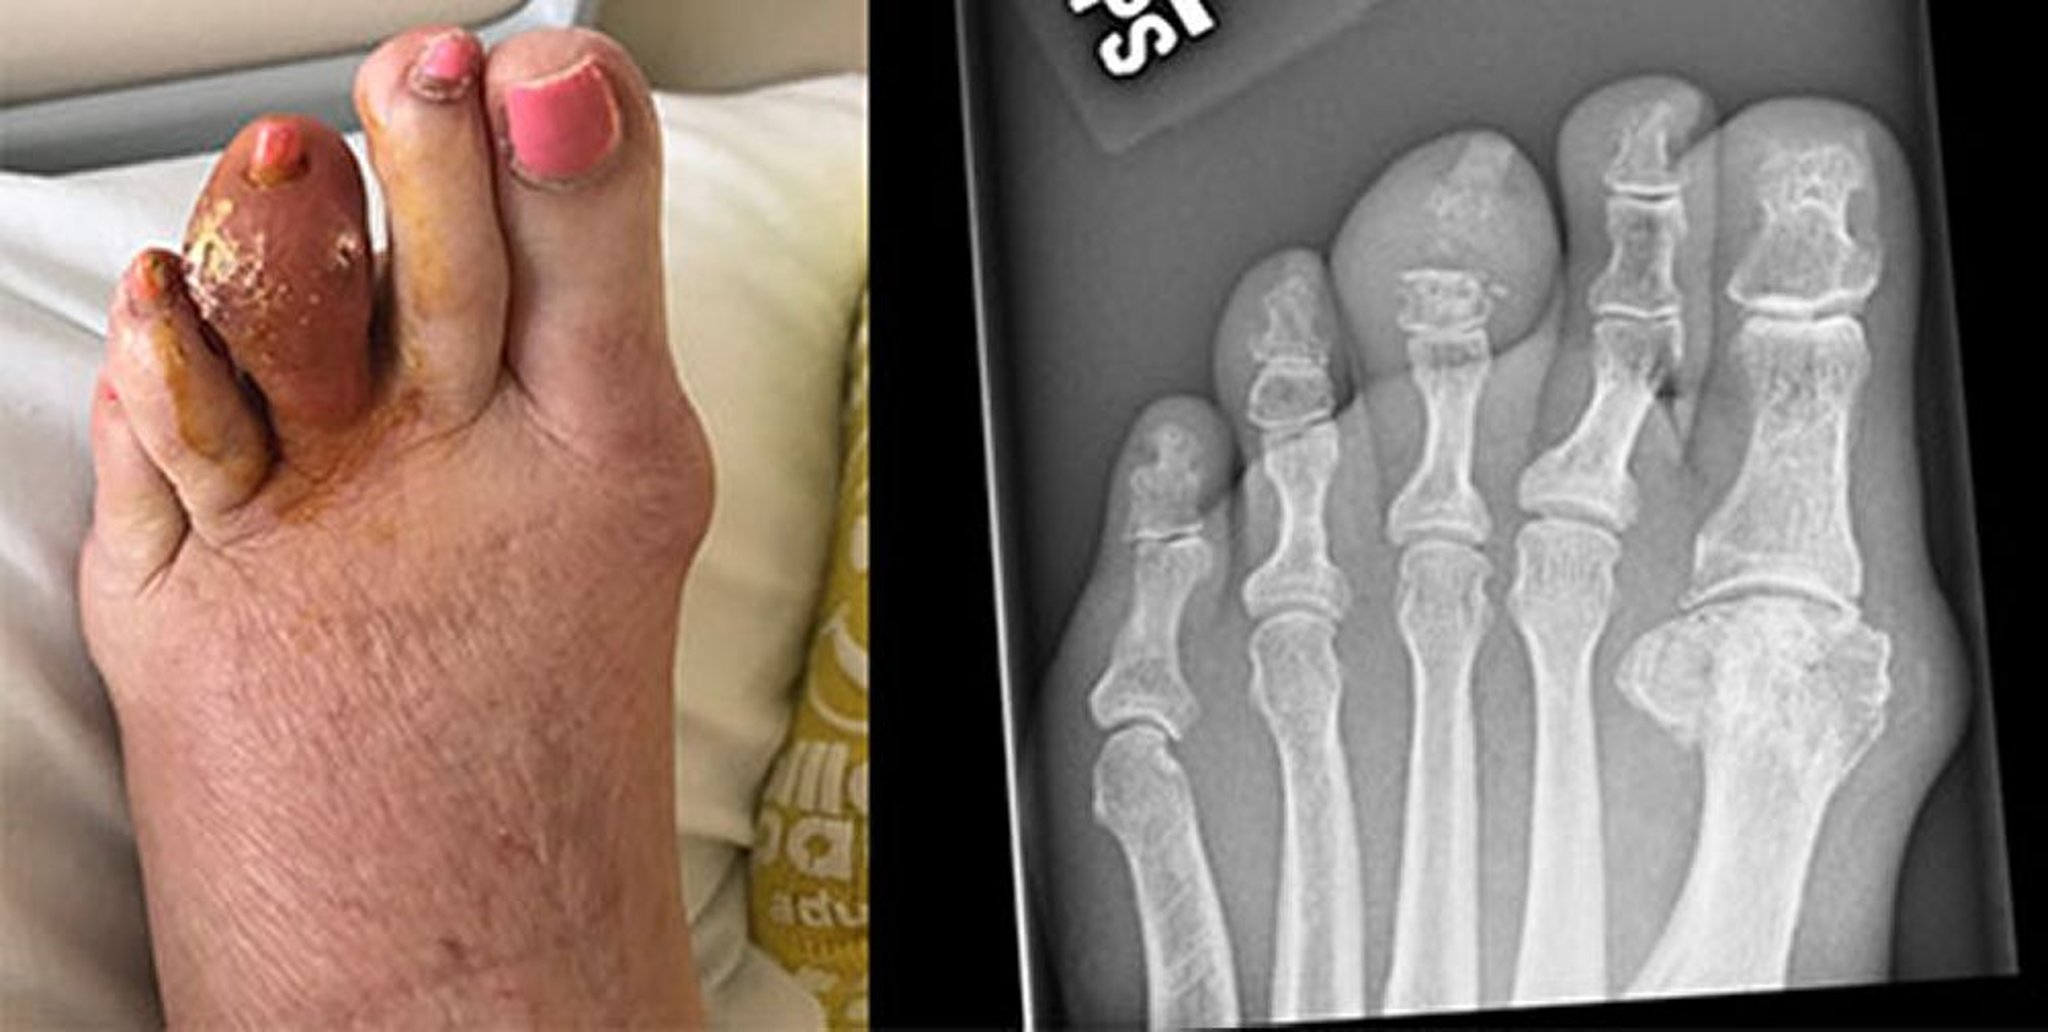

痛風結節

痛風患者には触知可能な痛風結節が生じるが,まれに急性痛風性関節炎の既往がない患者にそうした結節が生じることもある。通常は硬い黄色または白色の丘疹または結節であり,単一または複数である。様々な部位(一般的には手指,手,足,および肘頭またはアキレス腱の周辺)に発生しうる。痛風結節は,さらに腎臓および他の臓器ならびに耳の皮下にも発生することがある。変形性関節症のヘバーデン結節がある患者では,結節内に痛風結節が発生することがある。これは利尿薬を服用している高齢女性で最もよくみられ,劇的に炎症を起こして,炎症性の変形性関節症と誤診されることがある。通常は無痛性であるが,痛風結節(特に肘頭の滑液包中)は急速に炎症を起こし痛みを伴うようになることがあり,これは軽度または不顕性の外傷の後に多い。痛風結節は,皮膚を越えて突出することがあり,尿酸結晶のチョーク様の塊を排出する。その瘻孔が感染を起こすことがある。関節内および関節周囲の痛風結節は,最終的に変形と二次性変形性関節症を引き起こすことがある。

原因不明の関節疾患が遷延しているか,皮下または骨に痛風結節がみられる患者では,慢性痛風性関節炎を疑うべきである。第1中足趾節関節または他の罹患関節の単純X線が有用となることがある。それらのX線では,張り出した骨縁辺とともに軟骨下骨の打ち抜き病変を示すことがある(第1中足趾節関節で最もよくみられる);病変がX線で目に見えるようになるには直径が5mm以上でなければならない。関節裂隙は,典型的には疾患経過のかなり後期まで保たれる。通常は,罹患関節の慢性貯留液から得られる滑液所見で診断に至る。